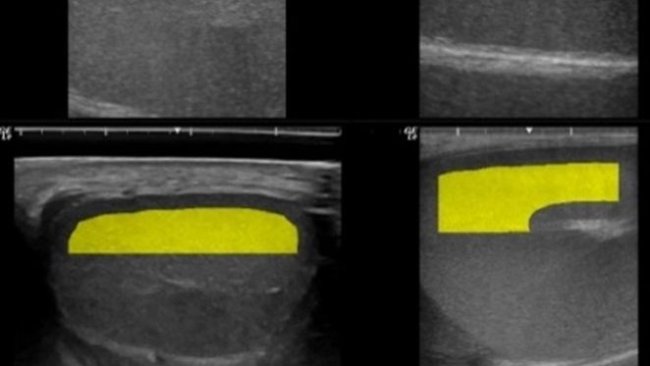

La tecnología Fertiboar permite predecir la calidad seminal del verraco basándose en medidas ecográficas testiculares previas a su primera colecta seminal.